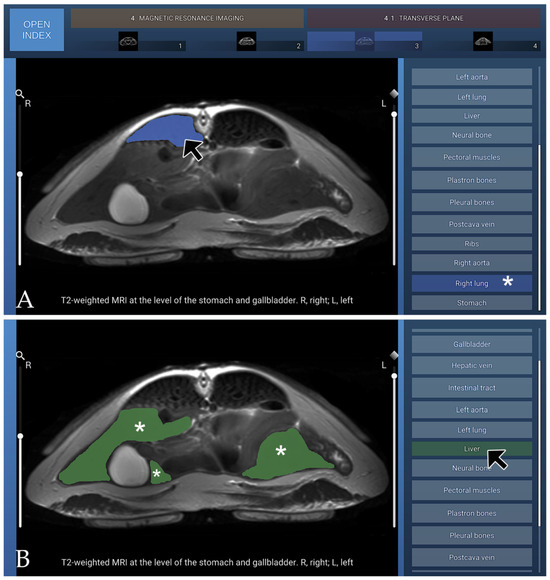

Anatomic Interactive Atlas of the Loggerhead Sea Turtle (Caretta caretta) Coelomic Cavity

The coelomic cavity of sea turtles is affected by congenital, developmental, traumatic, infectious, and organ- or system-specific disorders, making accurate anatomical knowledge essential for veterinary practice. This study presents an open-access, interactive two-dimensional (2D) anatomical atlas of the coelomic cavity of the loggerhead [...] Read more.

The coelomic cavity of sea turtles is affected by congenital, developmental, traumatic, infectious, and organ- or system-specific disorders, making accurate anatomical knowledge essential for veterinary practice. This study presents an open-access, interactive two-dimensional (2D) anatomical atlas of the coelomic cavity of the loggerhead sea turtle (Caretta caretta), developed using images obtained from osteology, gross anatomical dissections, computed tomography (CT), and magnetic resonance imaging (MRI). The atlas comprises six osteology images, sixteen anatomical dissection images, eight transverse CT images acquired using bone and soft-tissue windows, six three-dimensional (3D) volume-rendered CT images, and fourteen MRI images (four transverse, five dorsal, and five sagittal), all provided in PNG format. Relevant anatomical structures were segmented and colour-coded for each figure using manual layer-based segmentation software. The Unity 3D platform was employed for image visualisation and assessment, supporting the development of interactive two-dimensional content. This atlas serves as a useful interactive tool for anatomical learning and clinical reference for professionals and students engaged in the conservation of loggerhead sea turtles. Full article

Show Figures

Figure 1